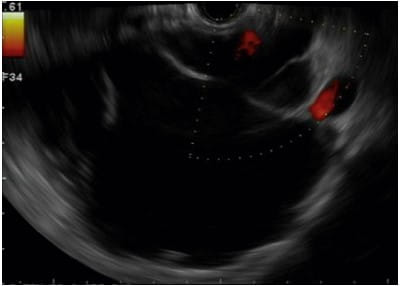

Pancreatic cystic lesions present a diagnostic challenge due to their diverse nature. While most of these lesions are benign, accurately identifying mucinous neoplasms like IPMN and MCN is crucial, as they may harbor malignancy or have malignant potential. Endoscopic Ultrasonography (EUS) plays a pivotal role in this differentiation process.

Despite its utility, the diagnostic accuracy of EUS based solely on cyst morphology is limited. This necessitates a more comprehensive approach combining various EUS features for reliable diagnosis.

A multifaceted diagnostic strategy is essential for accurate differentiation of pancreatic cysts. This approach includes EUS features analysis, fluid cytology, carcinoembryonic antigen (CEA) levels, mucin staining, and molecular markers assessment. Each of these elements contributes to a more accurate diagnosis, helping distinguish between benign and potentially malignant cysts.